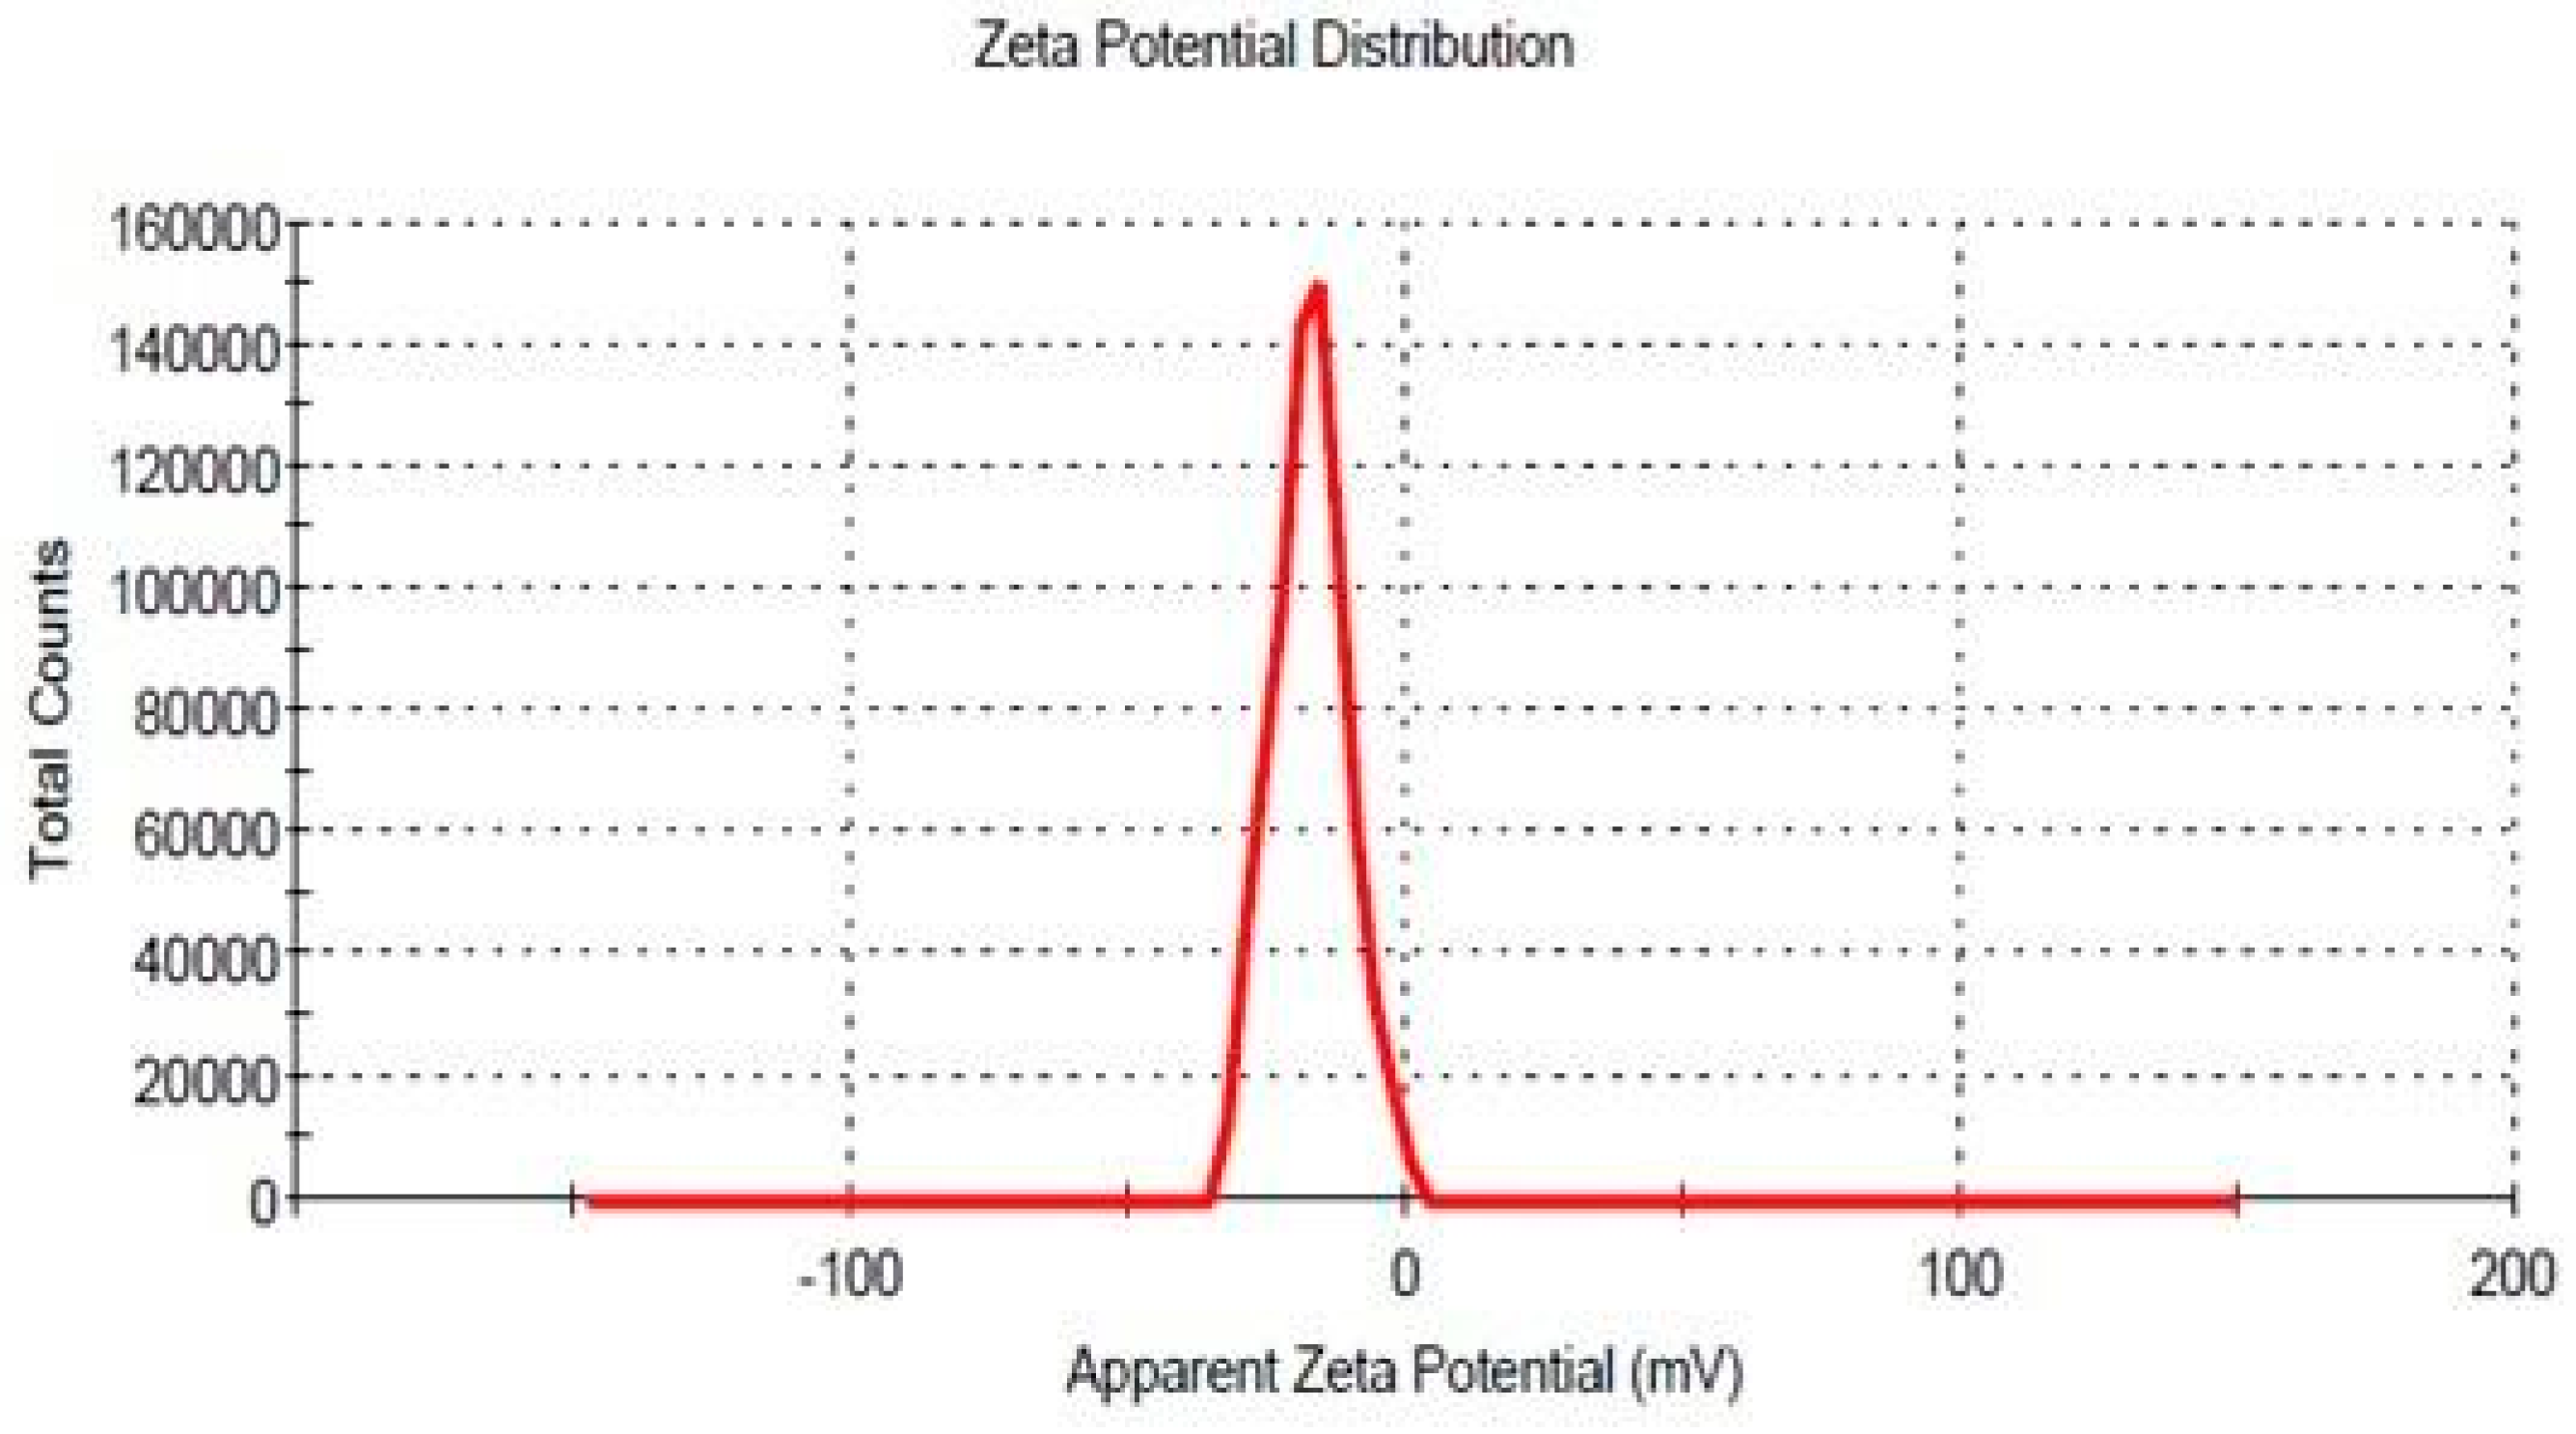

2.7.2. Zeta Potential

3.6.1. Zeta Potential